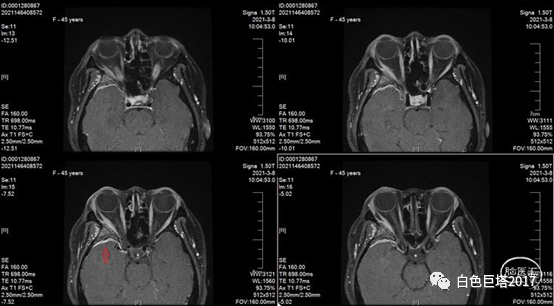

下图红箭头示磁共振增强提示局部脑膜强化

入院头颅CT检查提示右侧颞骨-眼眶后外侧壁骨质改变,眶内未见明显占位。报告考虑骨纤维异常增殖症可能性大。

入院讨论病情,患者以突眼为主要症状,无眼球活动障碍,无炎性症状,无眶内占位,无甲状腺功能异常。结合患者入院头颅眼眶CT重建检查及既往MRI表现,考虑蝶骨嵴脑膜瘤可能,同时不能除外颅骨纤维异常增殖症。

蝶骨嵴内1/3脑膜瘤进展可出现眶上裂综合征(III、IV、VI颅神经及V-1受累)或Foster Kennedy综合征(同侧视神经萎缩,对侧视乳头水肿)。而本例考虑蝶骨嵴外1/3脑膜瘤,累及蝶骨大翼,眶后外侧壁及颞部骨质增生,眼眶缩小,眼球前突,眼睑肿胀。